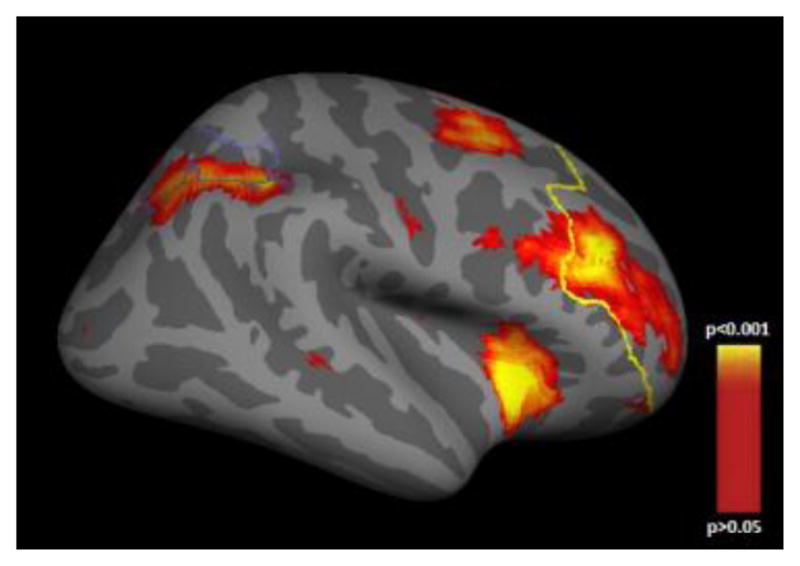

3.2 Functional MRI

Three CPLX2 SNPs (rs2443541, rs2243404, and rs4868539) were associated with load-dependent neural activity in working memory-related brain regions (DLPFC and IPS; see Fig. 1) in the schizophrenia sample. For both, rs2443541 and rs2243404, C allele homozygotes showed an increased neural activity when compared to T allele carriers (F(df=1,104) = 12.387, p = 0.001 and F(df=1,104) = 12.972, p < 0.001, respectively). The same was found for rs4868539 G allele carriers compared to A allele homozygotes (F(df=2,104) = 5.530, p = 0.005; see Table 2). According to Bonferroni-corrected post-hoc tests, the estimated residuals of the neural activity differed significantly between G allele homozygotes and A allele homozygotes (p = 0.024), as well as between heterozygotes and A allele homozygotes (p = 0.005), but not between G allele homozygotes and heterozygotes. We found no evidence for associations between working memory-related neural activity and any of the seven CPLX2 SNPs in healthy participants. Table 3 displays the test statistics and p-values for the linear mixed models of each SNP. For CPLX2 rs2443541 and rs2243404 the aforementioned effects were also determinable on a whole-brain level (see Online Resource 2.2).

Fig 1. FreeSurfer cortical parcellation of the DLPFC and IPS in the schizophrenia sample.

Cortical statistical map illustrating regions of working memory-related load-dependent neural activity in the dorsolateral prefrontal cortex (anterior outline) and the intraparietal sulcus (posterior outline) in the schizophrenia sample. This map is shown on the inflated surface of the standard average subject allowing visualization of data across the entire cortical surface without interference from cortical folding.